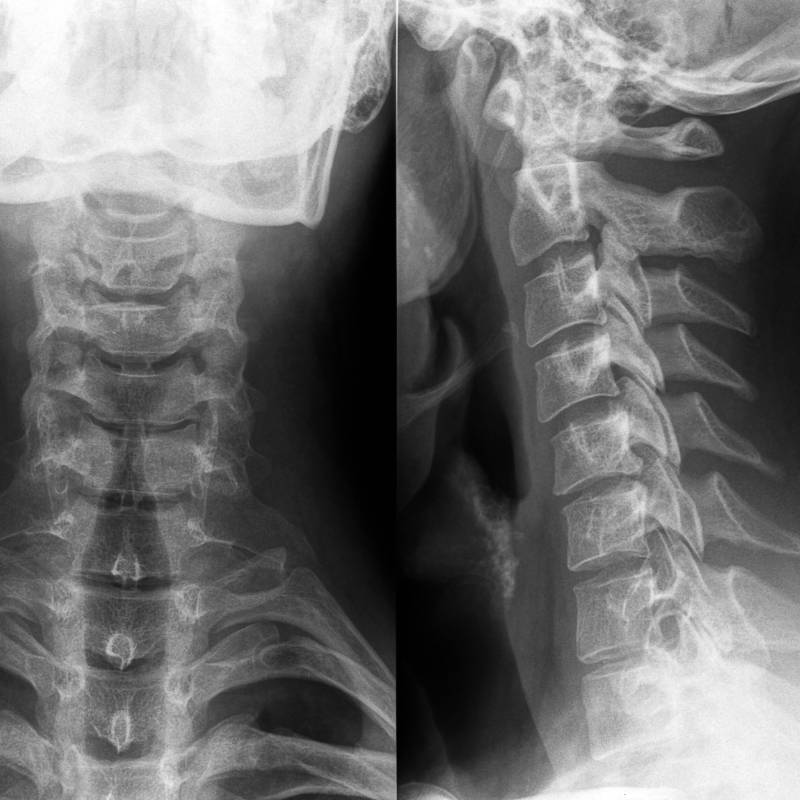

Digunakan untuk mengenal pasti masalah pada tulang belakang.